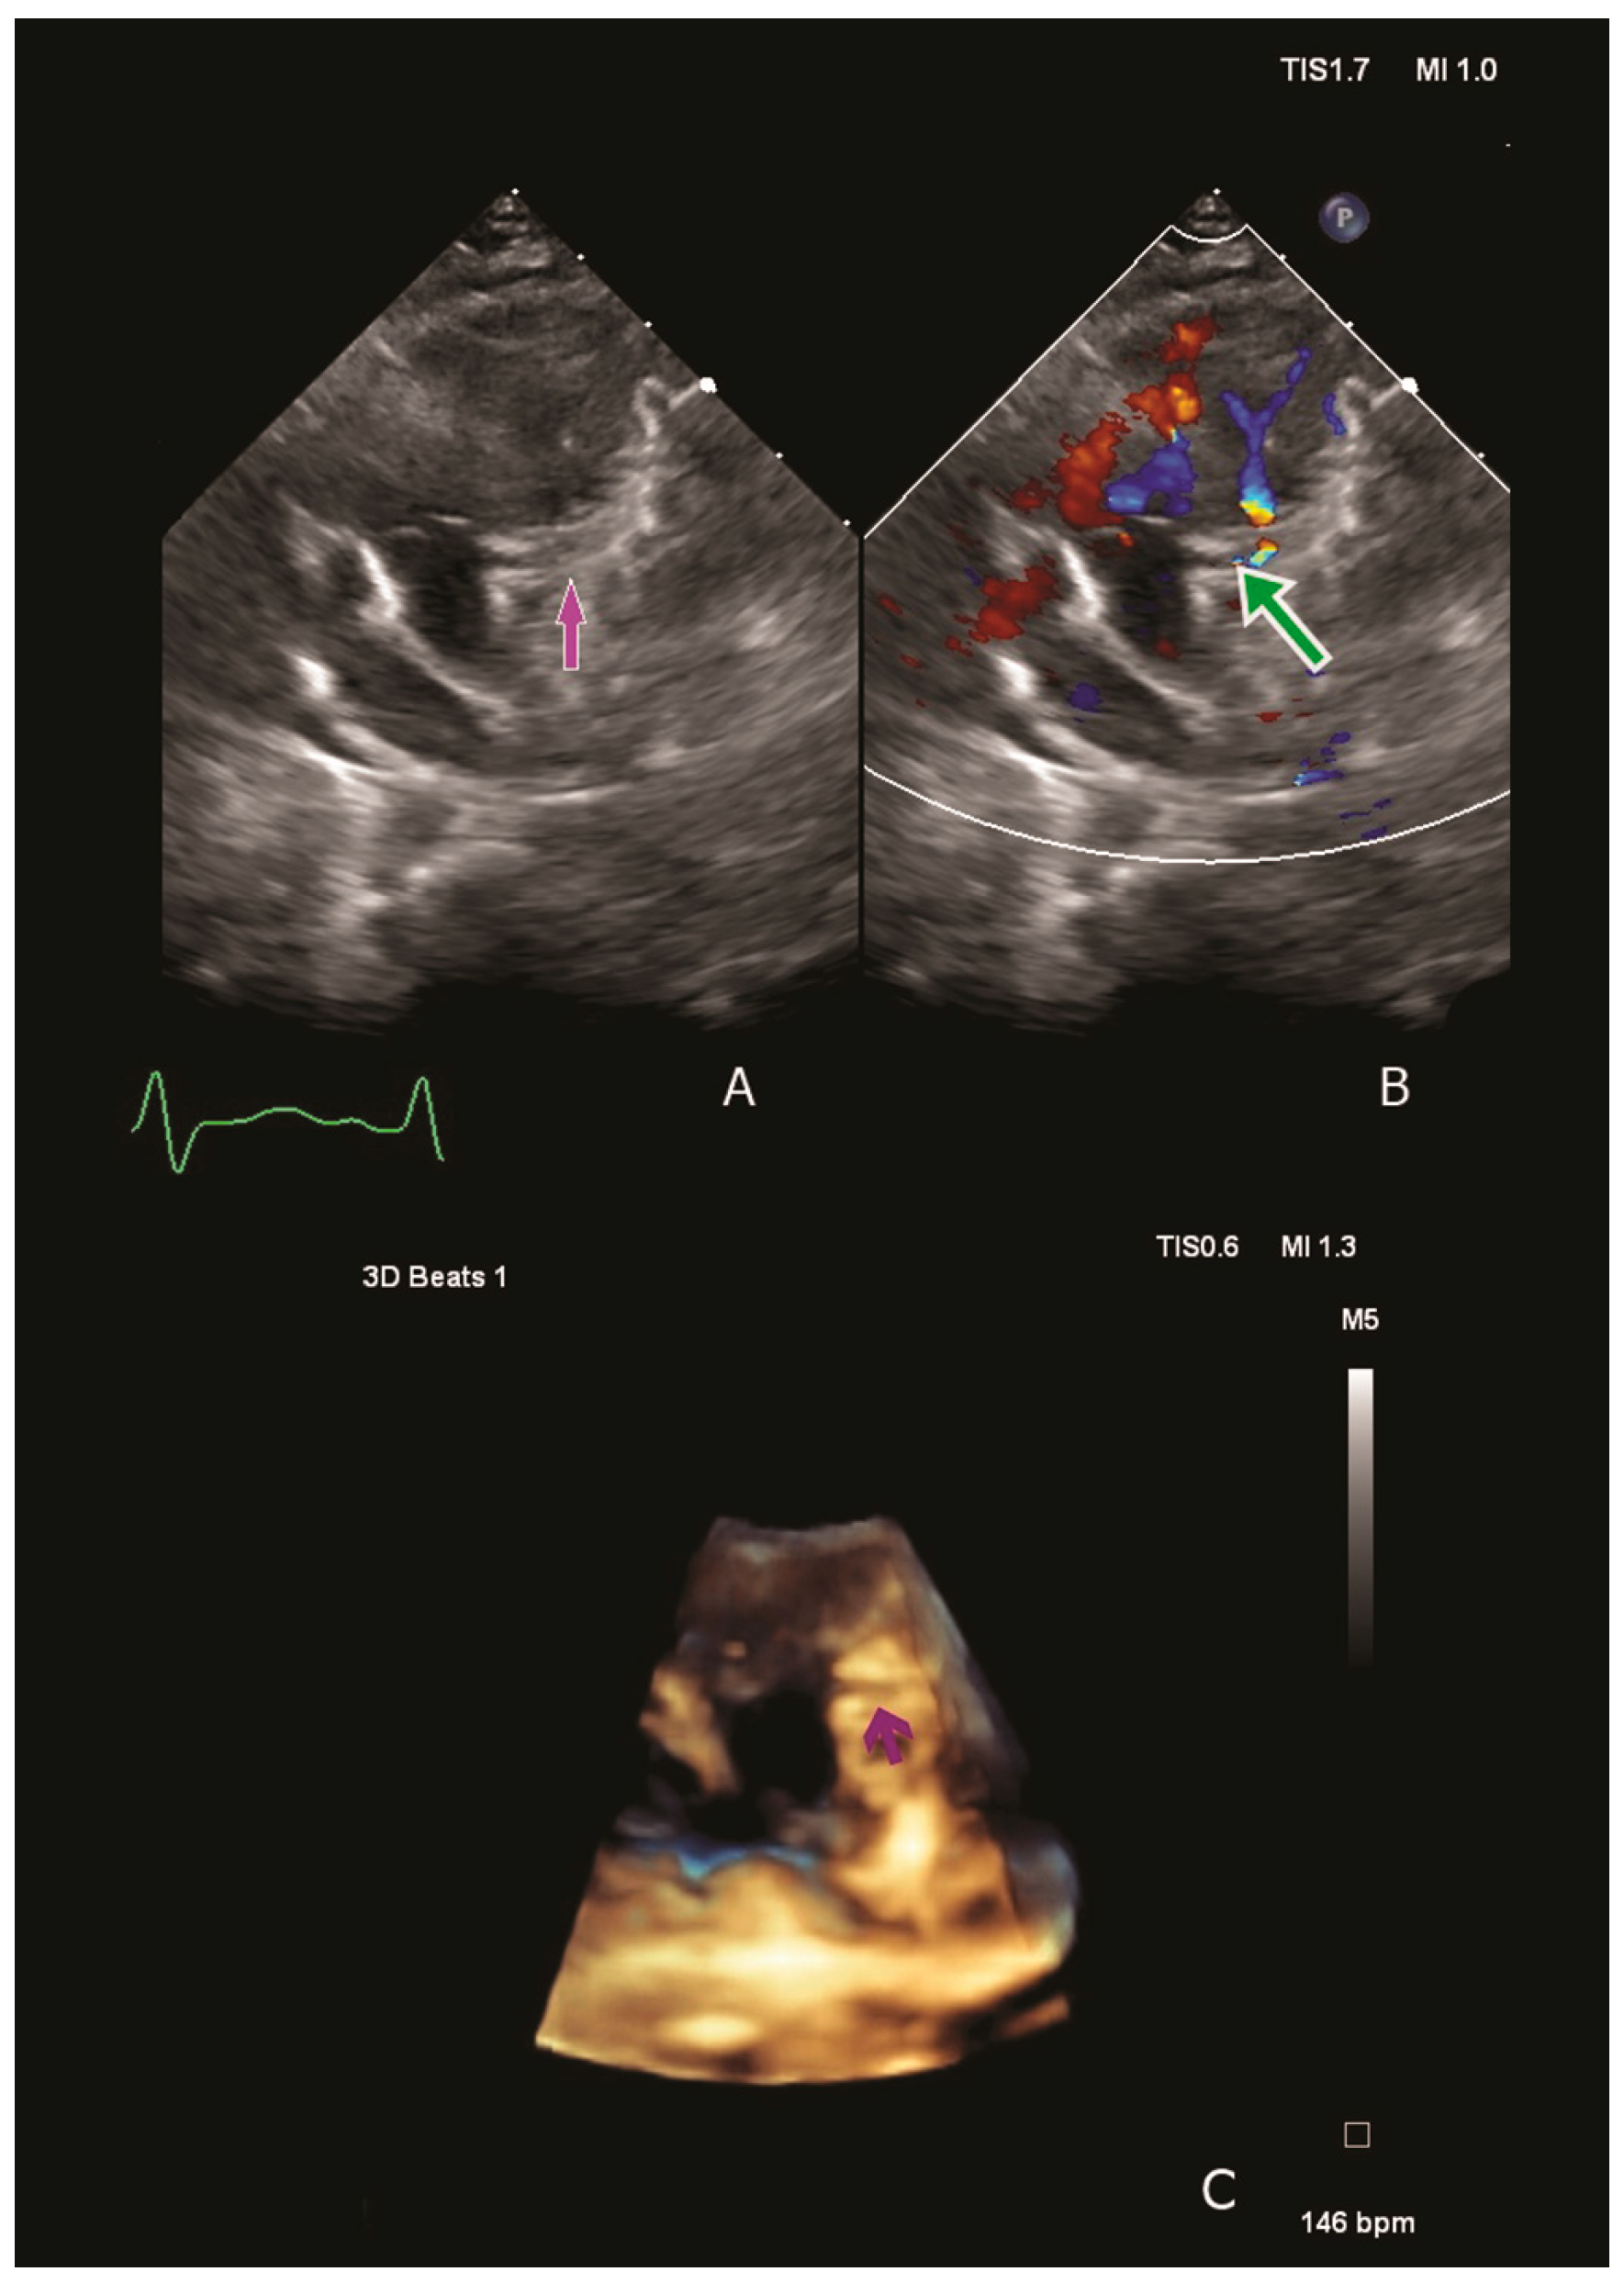

Physical examination revealed low cardiac output and acute HF symptoms (pale skin with cold extremities, respiratory distress, tachycardia, a 4/6 holosystolic murmur at the left side of the sternal border, hepatomegaly). Laboratory tests indicated elevated serum creatinine levels, suggesting an acute pre-renal failure due to severely reduced systemic output. Moreover, significantly elevated NT-proBNP, Troponin T hs and Lactate levels were observed (60,477 pg/mL, 138 pg/mL and 6.3 mmol/L). Chest radiography revealed cardiomegaly, and the electrocardiogram revealed septal ischemia with a characteristic ALCAPA QR pattern in lateral leads. A transthoracic echocardiography revealed severe dilatation of the LV compressing the right cavities and severe mitral valve regurgitation with a dilated mitral annulus. The origin of the LCA from the pulmonary artery was visualised using two-dimensional and three-dimensional techniques. Color Doppler revealed retrograde flow from the pulmonary artery into the LCA (Figure 1).

Figure 1.

Two/three-dimensional echocardiography confirming ALCAPA diagnosis. We visualise the origin of the left coronary artery from the pulmonary artery: the purple arrow (A,C) and colour Doppler flow confirming the retrograde flow from the pulmonary artery into left coronary artery- the green arrow (B).